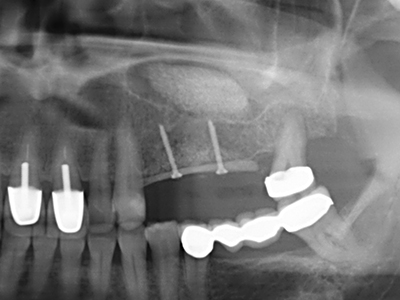

Quando le procedure chirurgiche vengono eseguite sull'osso nelle immediate vicinanze di strutture sensibili, come vasi sanguigni o nervi, gli strumenti rotanti pongono un rischio significativo di lesione iatrogena. I dispositivi piezoelettrici possono essere utili per la preparazione delle coperture ossee e la rimozione del tessuto duro in prossimità dei nervi, in particolare per la loro esposizione dopo una lesione iatrogena, ma anche durante la lateralizzazione dei nervi per le procedure di resezione e ricostruzione o il posizionamento di impianti (figg. 17-20). Il contatto leggero tra puntina piezoelettrica e nervo non causa generalmente danni, ma se si procede senza prestare attenzione con movimenti a sega o raccordi con residui di substrati ossei possono verificarsi danni al nervo temporanei o anche permanenti. Il rischio di danno, tuttavia, è considerato sostanzialmente inferiore al rischio presente utilizzando seghe o frese (Pereira, Gealh et al. 2014).